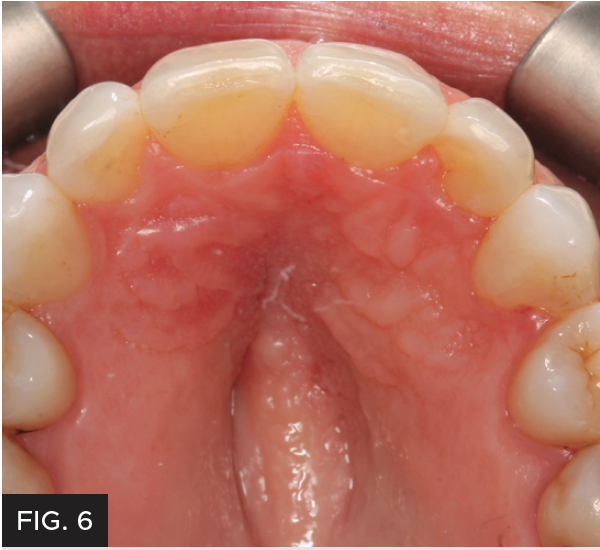

After the patient’s crowding issues had been corrected with orthodontics, the gingival display at #7 was excellent. All that remained was to restore the tooth to proper dimensions. (FIG 3 & 4) Different treatment options were discussed with the patient, including a composite veneer, Class IV restoration, and minimal-preparation porcelain veneer. Each option’s expected longevity was explained. The patient chose to have the tooth restored with a Class IV mesial-incisal-distal restoration.

Photographs were taken to evaluate aesthetic outcome. The patient was shown her new restoration and was pleased with the results. The patient returned a few weeks later for a final post-op check. The tissue healed well after removal of the attachments. Proper canine function was confirmed and lateral disclusion of the lateral was obtained which is ideal with a Class IV restoration on such a small sized tooth.12 The final pictures2 and post-op x-rays were taken. (FIG 8 & 9)